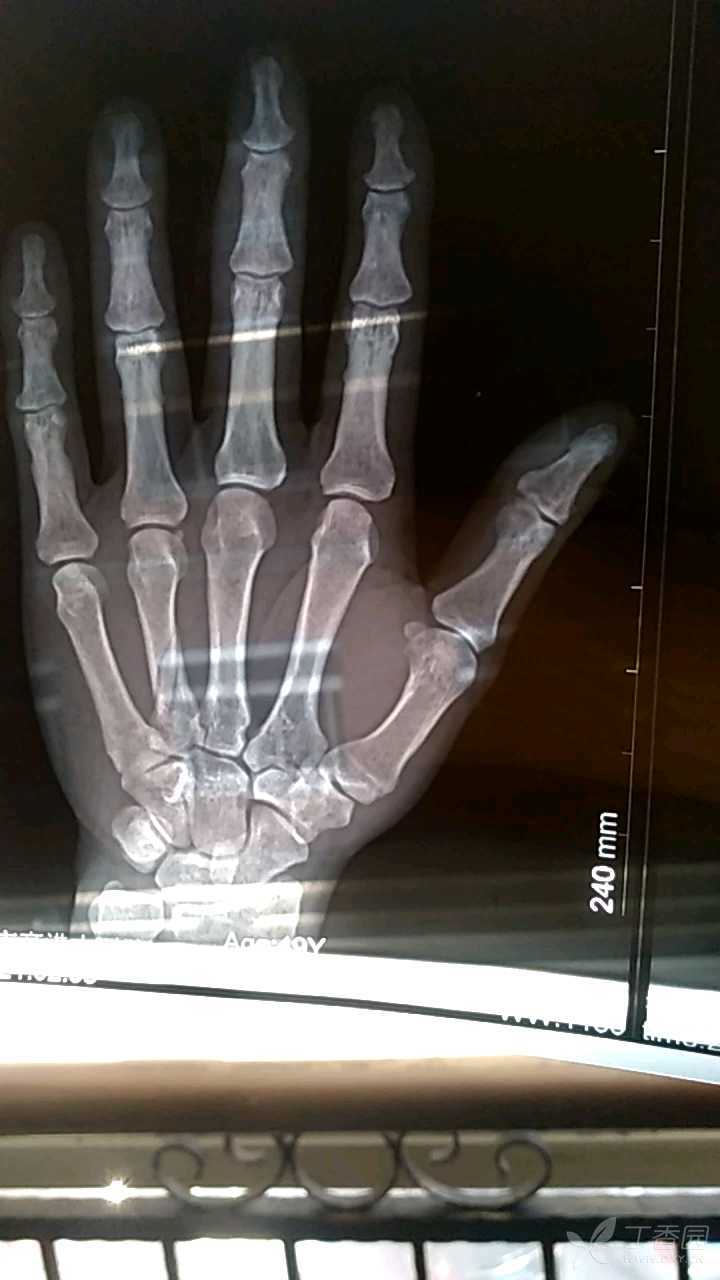

左手无名指近节指骨基底部横行骨折复查,正位,断端对位对线良好